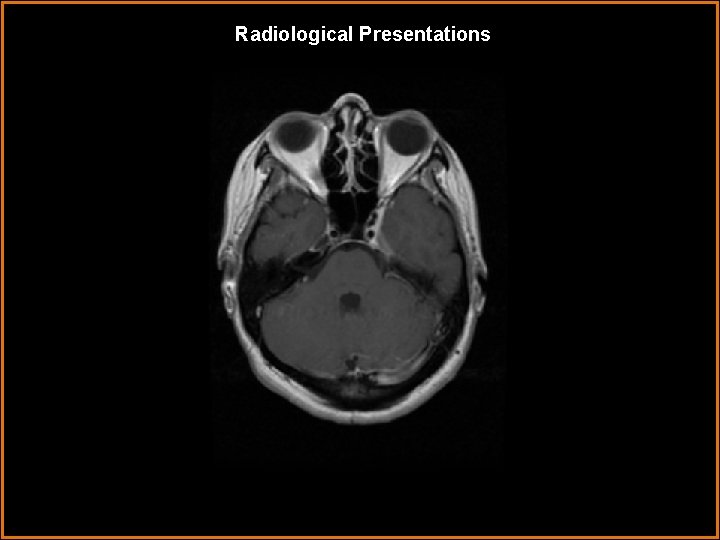

Findings and Differentials Findings: Pre and Post contrast T 1 -weighted images demonstrate enhancing soft tissue within the left cavernous sinus, with extension of the enhancement through the left foramen ovale along the 3 rd cranial nerve. The carotid flow voids are normal. The CT image in bone window demonstrates the foramina ovale to be symmetrical and not expanded. Differentials: • Tolosa-Hunt Syndrome • Sarcoid • Meningioma • Perineural spread into cavernous sinus via V 3 • Infection